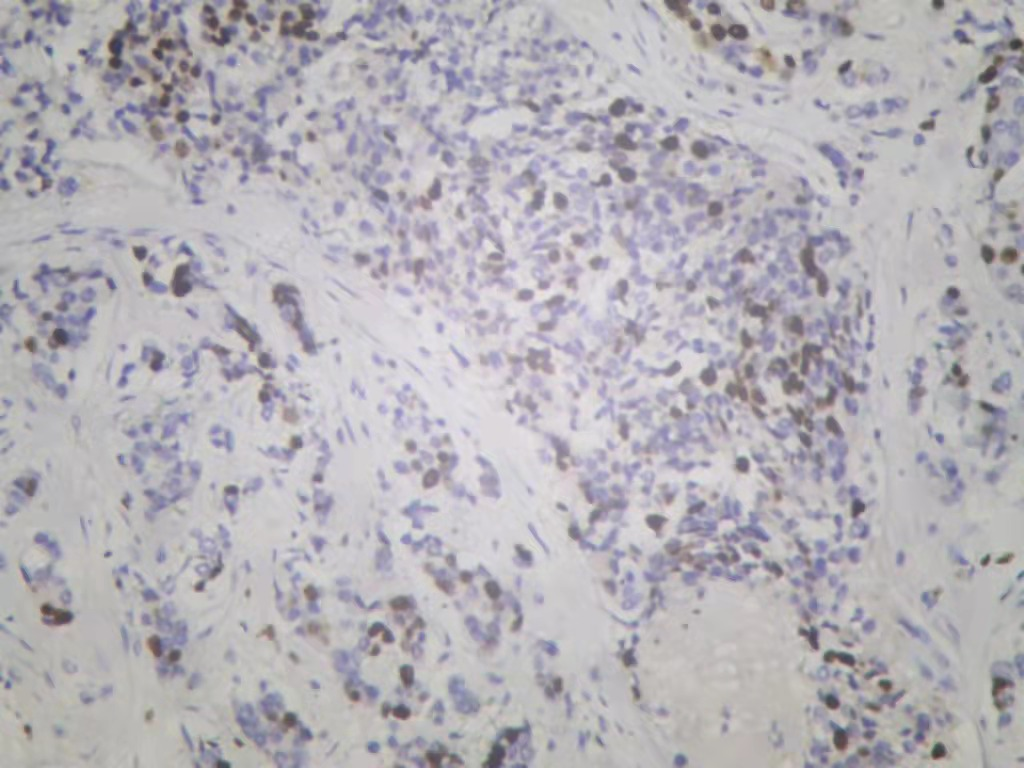

图3. 免疫组化Cerb-B2

图4. 免疫组化PR

图5. 免疫组化ER

图6. 免疫组化Ki-67